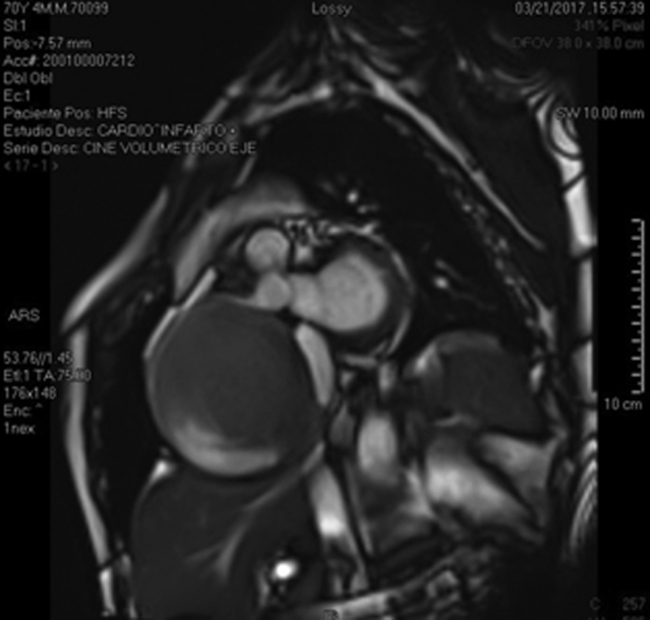

Se presenta el caso de un paciente de género masculino de 70 años, extabaquista con antecedente de hipertensión arterial y dislipemia. Ingresa por infarto agudo de miocardio de cara inferior al que, por demora en su arribo al hospital, no se le administró terapia fibrinolítica por encontrarse ya fuera de la ventana terapéutica. Evoluciona con episodios de dolor precordial opresivo, sudoración y disnea que se exacerban con los cambios posturales, hipotensión ortostática y presíncope. Al interrogatorio refería presentar episodios presincopales y disnea de varios meses de evolución. En el ecocardiograma transtorácico se evidencia una imagen redondeada con flujo en su interior que comprime las cavidades cardíacas derechas. Se realiza una angiotomografía que caracteriza dicha imagen de 103 x 90 mm de diámetro, bordes netos y contenido homogéneo con realce de contraste endovenoso en su interior. Se realiza angiorresonancia cardíaca que, además, evidencia la relación de la arteria coronaria derecha con la imagen redondeada con flujo en su interior como se muestra en la Figura 1.

Imagen de la resonancia magnética cardíaca que muestra una imagen redondeada con líquido en su interior y que corresponde a la arteria coronaria derecha